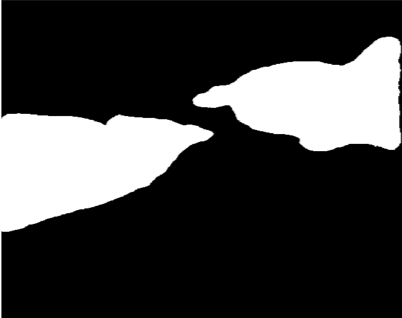

Our challenge was made up of 3 sub-problems. The first was binary instrument segmentation, where each frame was separated into da Vinci Xi instruments and a background class, which contained an ultrasound probe, surgical clips and porcine tissues. The second task was instrument part segmentation, where we scored the participants on whether they could correctly segment each articulating part of the instrument (see Fig. 3). Our final task was to segment and classify the instruments (see Fig. 4).

We provided the first 225 frames of 8 sequences as training data and kept the last 75 frames of those 8 sequences as test data. 2 of the full 300 frame sequences were kept as test sequences. Test labels were kept hidden from the participants. Our datasets contain 7 different robotic surgical instruments. The Large Needle Driver, Prograsp Forceps, Monopolar Curved Scissors, Cadiere Forceps, Bipolar Forceps, Vessel Sealer and additionally a drop-in ultrasound probe, which is typically held in the jaws of the Prograsp Forceps instrument. Samples from the training datasets are depicted in Fig. 2 and examples of the different instrument types are shown in Figure 3 and 4.

IV-C Parts Segmentation

Our second challenge was on instrument part segmentation where the participants were challenged to divide the binary instrument labels into a shaft, wrist and jaws. As in the binary segmentation challenge, the drop-in US probe and other man-made devices as well as all anatomical objects were to be labelled as background. We compute the mean IoU for each frame of each dataset and for frames where no instance of a class occurred, such as when the shaft is withdrawn completely from the field of view. Nine teams participated in this challenge, the only team abstaining was from IIT Delhi.